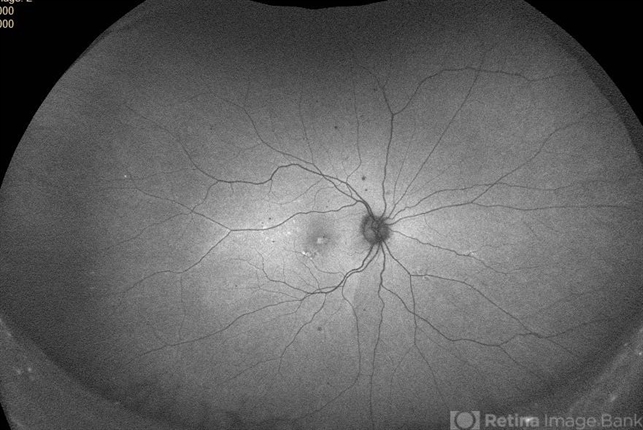

- congenital stationary night blindness (CSNB)

Scanning laser ophthalmoscope

Optos Daytona - Description

- Oguchi's disease showing the Mizo Nakamura phenomenon with autofluorescence image showing normal Fundus